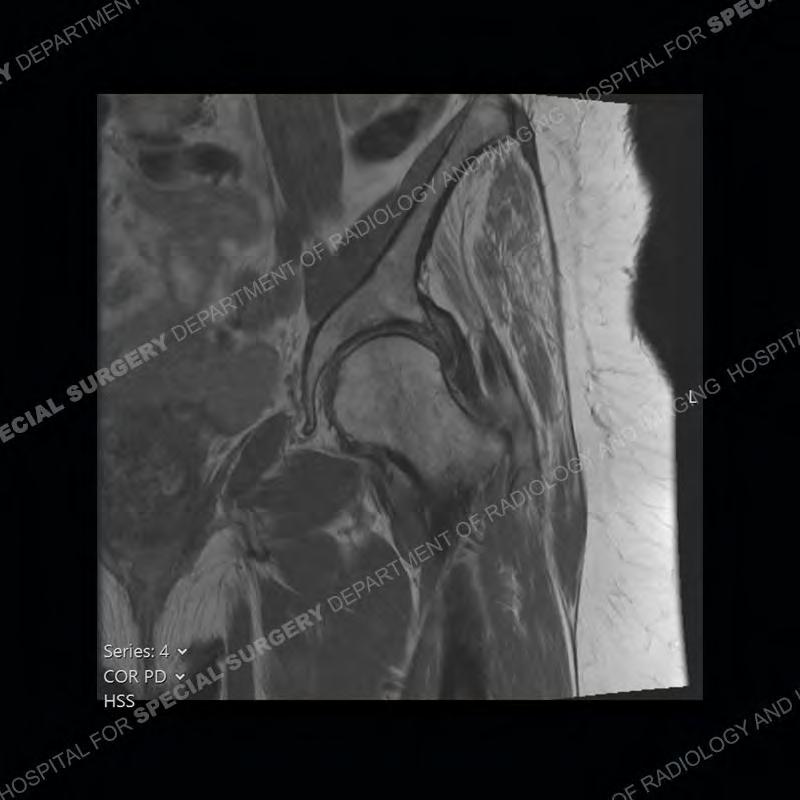

The radiograph is not particularly contributory in this case. The MRI demonstrates markedly abnormal architecture of the gluteus minimus and anterolateral band of the gluteus medius. Portions of the tendons are high signal, portions are highly attenuated, and portions are disrupted. A large, complex fluid collection is present in the adjacent soft tissue.

Diagnosis: Gluteal Tendinosis and Disruption with Complex Trochanteric Bursal Collection

Not as much of a diagnostic dilemma as many of the other cases shown but just a nice example of the pathology seen of the gluteal tendons and a cause of trochanteric pain. Although, frequently thought of in isolation, trochanteric bursitis or bursal thickening is much more commonly a reactive change to underlying pathology of the subjacent gluteal tendons. The gluteus medius is divided into a posterior band and an anterolateral band. Tendinosis and partial tearing very commonly will involve the gluteus minimus and especially the more posterior fibers and then propagate into the anterior lateral band of the gluteus medius. Involvement of the posterior band of the medius is much less common and engenders a marked degree of functional impairment.

The bursae about the greater trochanter can be a little bit confusing especially given the terminology. Trochanteric bursitis is implied to mean the subgluteus maximus bursa which is present deep to the maximus and just lateral/superficial to the trochanter. That is the bursa involved in this case. In this case the complexity of the bursa relates to the tendon tearing with inflammatory change and probably hemorrhage accounting for the complexity. Two other, less frequently involved bursa are also present. The subgluteus medius and subgluteus minimus bursa are found just deep to the named tendons. Although pathology does frequently follow the previously described pattern it is possible to have isolated pathology to either the medius or minimus.